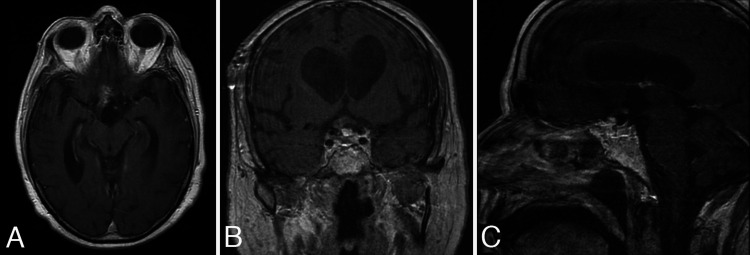

FIG. 5.

Postoperative MRI. Axial (A), coronal (B), and sagittal (C) contrast-enhanced T1-weighted images. Majority of the tumor was resected and there was minimal residual enhancement in the region of the chiasmatic cistern and anterior third ventricle.